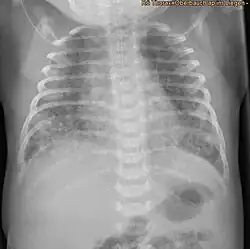

| X-ray showing the extent of lung epithelial damage in response to meconium seen in neonates with meconium aspiration syndrome. | |